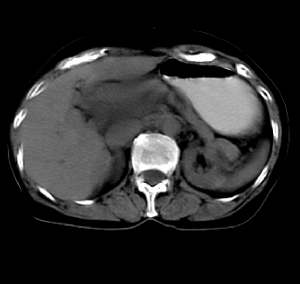

患者无任何不适及阳性体征,超声体检时发现,未做增强扫描。囊影密度均匀,ct值略高于水,囊影壁薄光滑,囊内密度均一。定性诊断不难,应是个囊肿。请大家做个定位诊断

1.无临床症状。2.小网膜囊组织受压推移。3.肝内胆管正常。纵上3点,考虑小网膜或肠系膜囊肿可能性大,最好mpvr多平面重建。

病灶上部层面与肝脏交界清楚但不太截然,下部层面与肝之间可见线状高密度带,考虑由囊块压迫肝实质形成,考虑caroli氏病,其次考虑左肝囊肿向下向肝外生长,另外其他来源囊肿及消化道重复畸形不排除